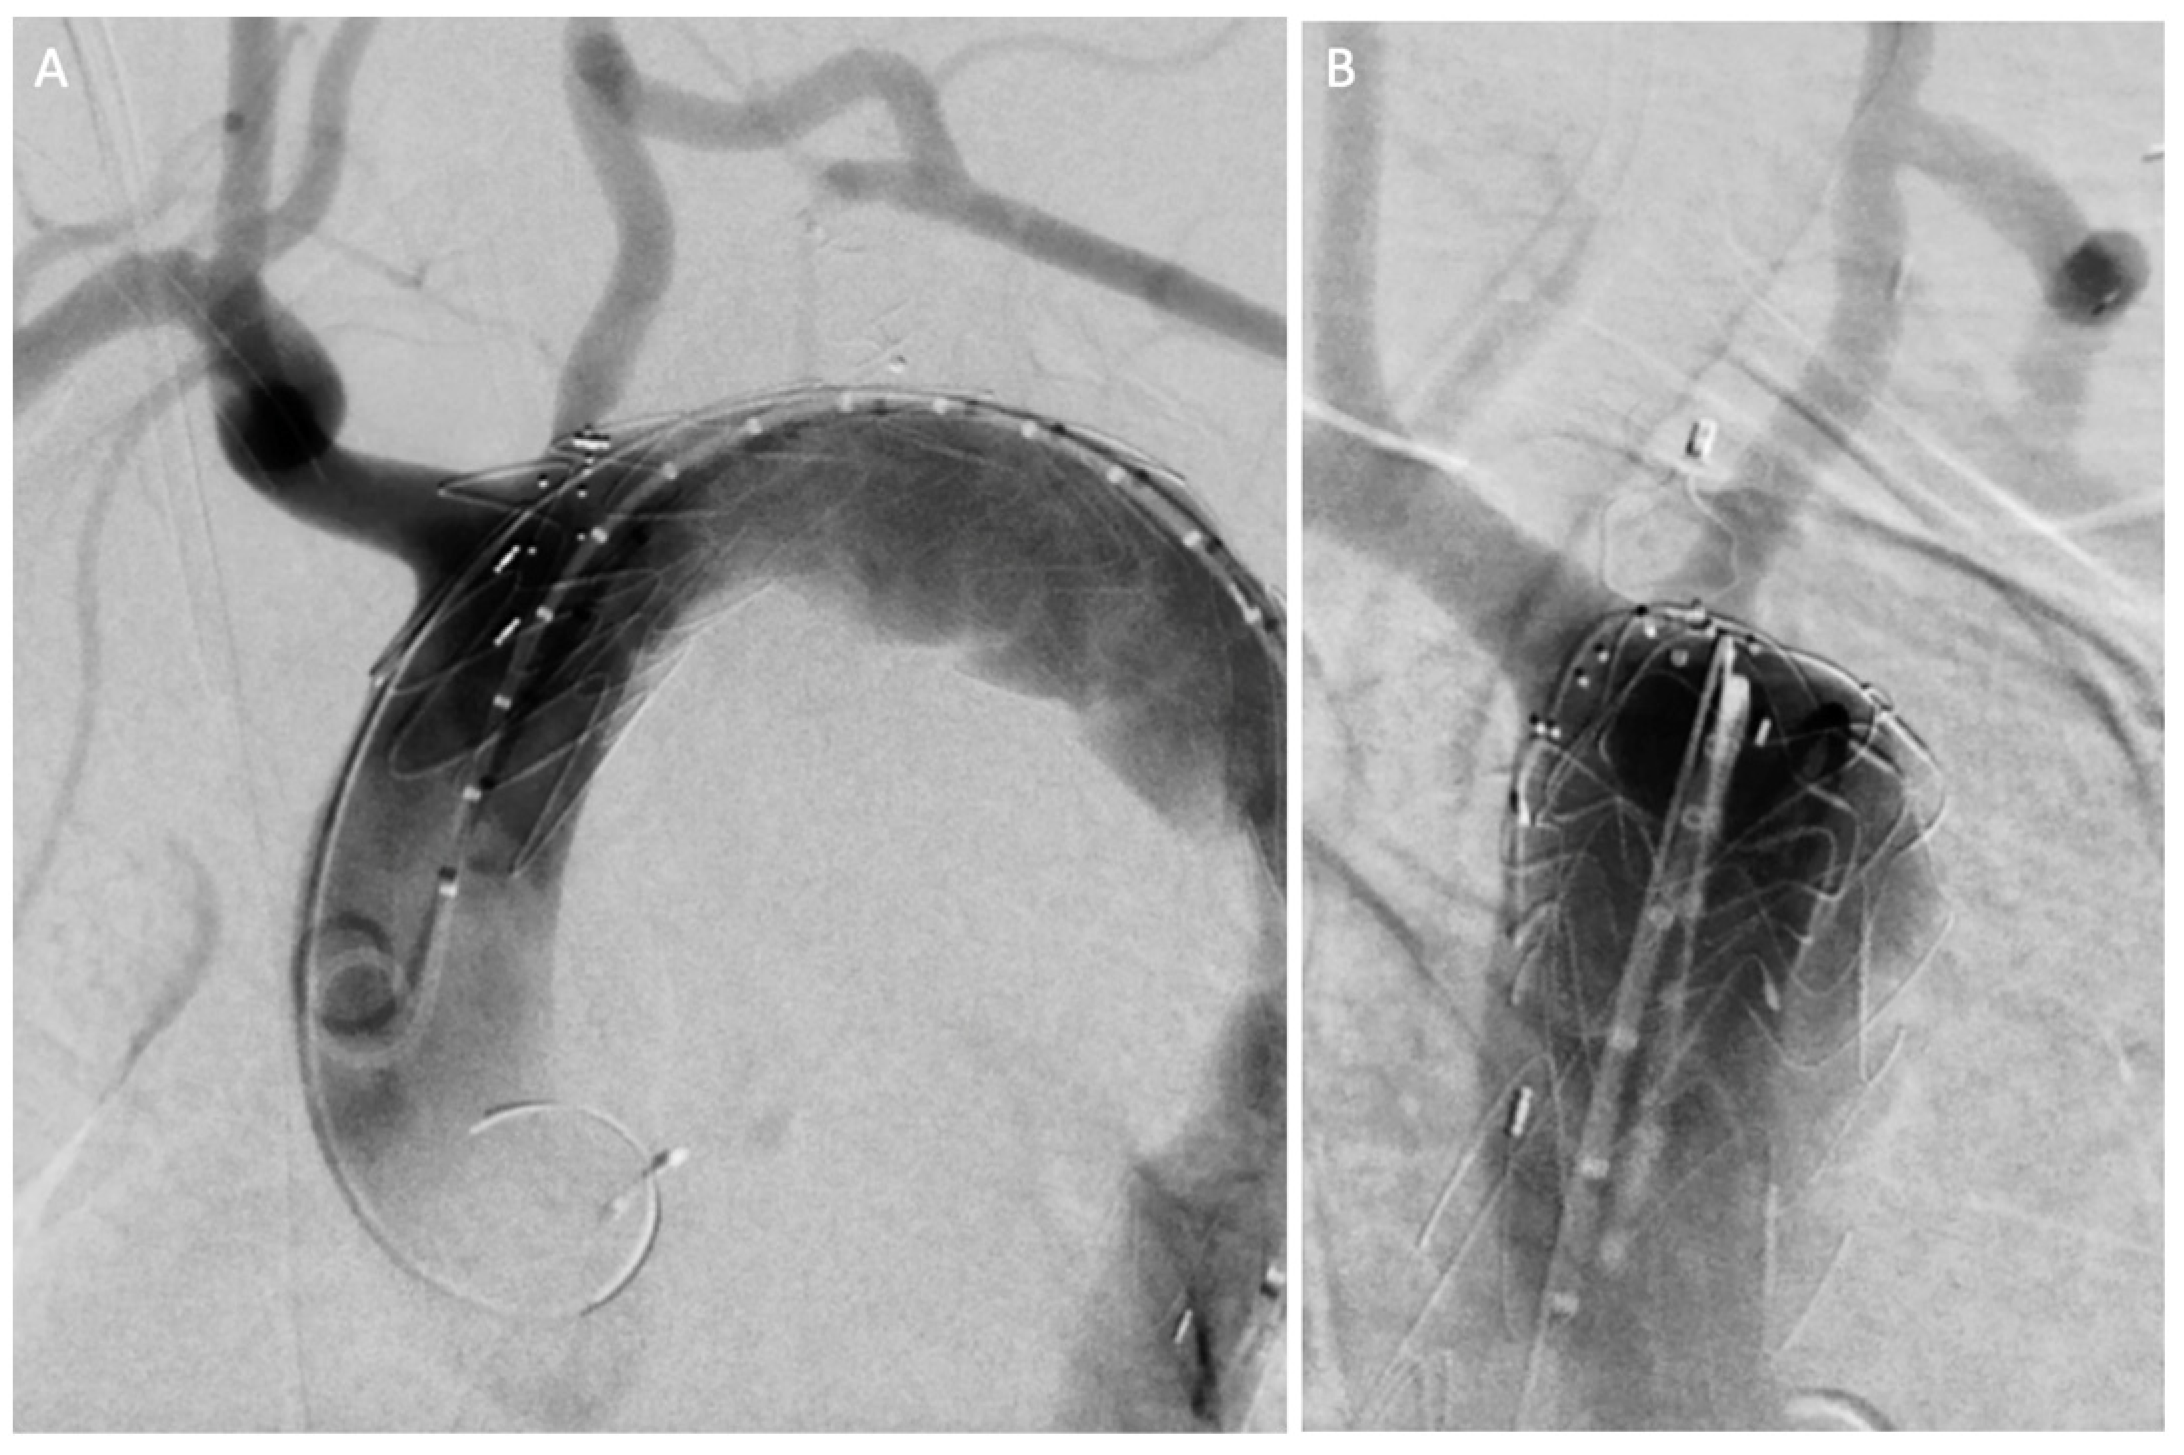

2.2. Case 2

| Current Case-2 | 46 | M | Aortic arch | Asymptomatic | 21 years | Hybrid (carotid-subclavian bypass + TEVAR) |